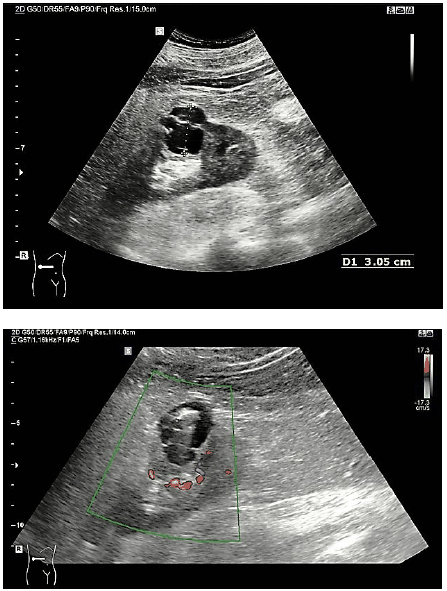

Paciente, 38 anos, sexo masculino, comparece para realizar ultrassonografia abdominal. Assintomático; exame solicitado para perícia médica em concurso público, em que foram observadas as seguintes imagens:

Considerando o caso hipotético, assinale a classificação dessa lesão de acordo com a classificação de Bosniak.